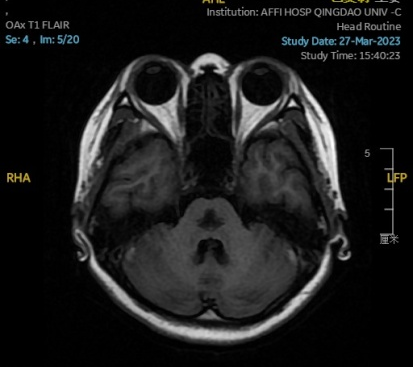

2023.03.27颅脑MR平扫示双侧基底节区及桥脑异常信号,考虑渗透性脱髓鞘综合征,较前范围略减小,请结合临床,见图4。

图4 2023.03.27双侧基底节区及桥脑见对称性片样长T1长T2信号,FLAIR呈高信号,较2023-02-24MR所示范围减小。脑室、脑池、脑沟、脑裂未见明显异常,中线结构居中。